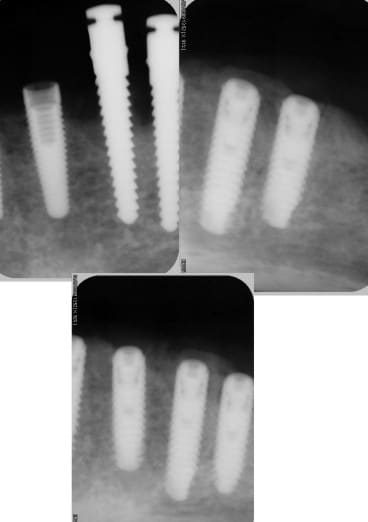

le pano

cicatrisation OK

pas de douleurs

pour le moment RAS

la suite le 25/08

combiné de mini expansion et classique implants courts 8 et 6 mm 4 et 4,6 de diam.

fente verticale, decharges latérales expanseurs, forets pour finir, implants lisse et pose de 3 Axioms